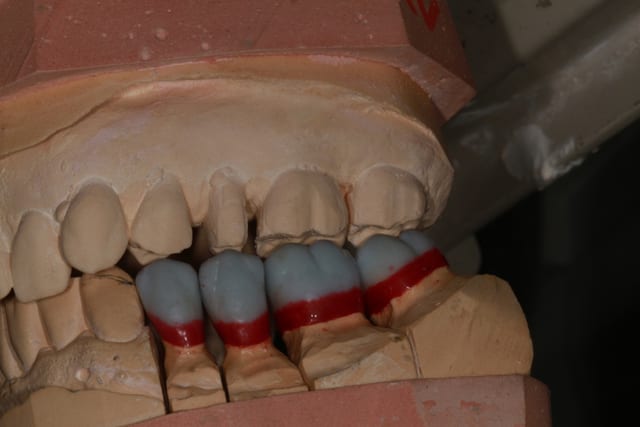

Empreinte, détourage et préparation des cires avec une occlusion différente de celle du wax up, un peu plus de DV

Le trait rouge sur les incisive donne à peu de chose prêt l'origine...